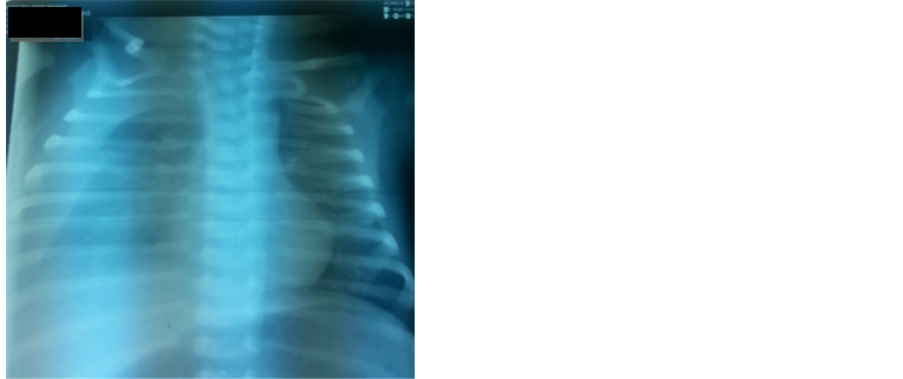

The Clinical examination of the newborn on admission revealed a moderate respiratory distress quoted 3/10 by the Silverman score, and decreased breath sounds on the right side of the chest. The Saturation of oxygen was 90% on 1 l/min of oxygen. The chest X-ray (Figure 1) and CT scan revealed an important right-sided pleural effusion and signs of pulmonary infections.

Figure 1. The chest X-ray performed at the admission showing a right pleural effusion.